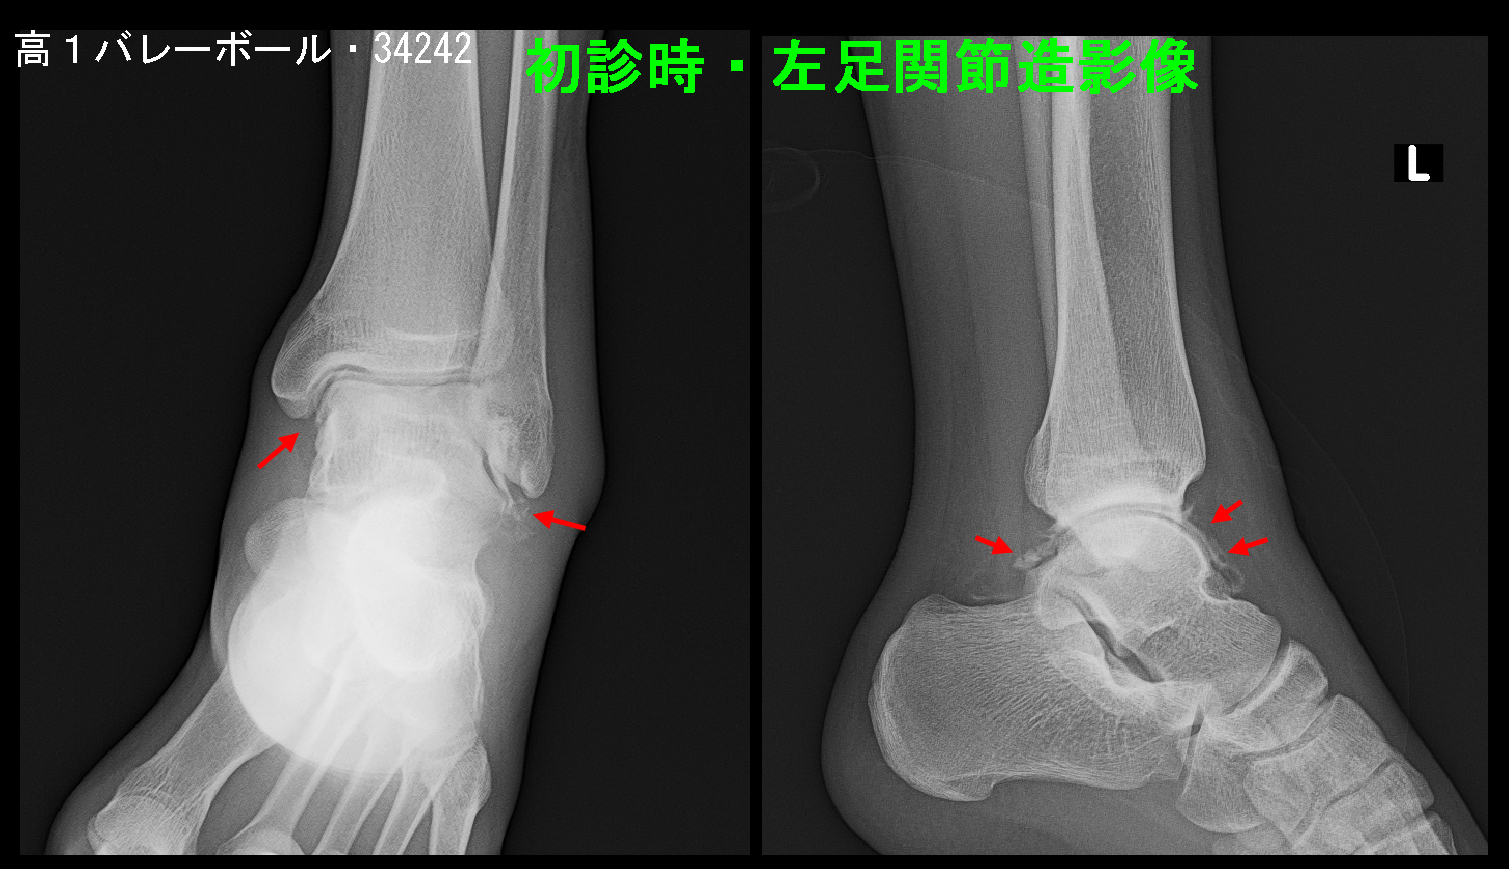

受診時両側の足関節レントゲン像ですが、健側の右足関節では足関節の内果・外果部の皮膚は骨の直ぐ上となりますが、患側の左足関節では外果部の皮膚は骨から分厚くなっています(赤矢印)。外傷による腫脹の結果です。外果部と内果部を結ぶ幅は健側では85mmで、患側は97mmで、周囲径としては(円周率をかけた)3.8㎝の差でズボンのサイズとしても4㎝も違うとかなり腫れていることが推察されます。

初診の4日後の5月4日にギプスシーネ固定のチェックのために受診してもらうと、患者さんはギプスシーネを外して受診し、「普通に歩けるので練習を始めたい」と言ってきました。

その時のレントゲン像ですが、97mmあった左足関節幅は88mm(健側との差は3mm)に軽減していました。原則私は患者さんの意向に沿った対応を心がけているので、「じゃ、やってみたら」と答えましたが、練習を開始すれば痛みと腫れが再発して、受診してくることになるだろうと思っていましたが、その患者さんは再診されることはありませんでした。治療した私も驚くほどの治療効果でした。